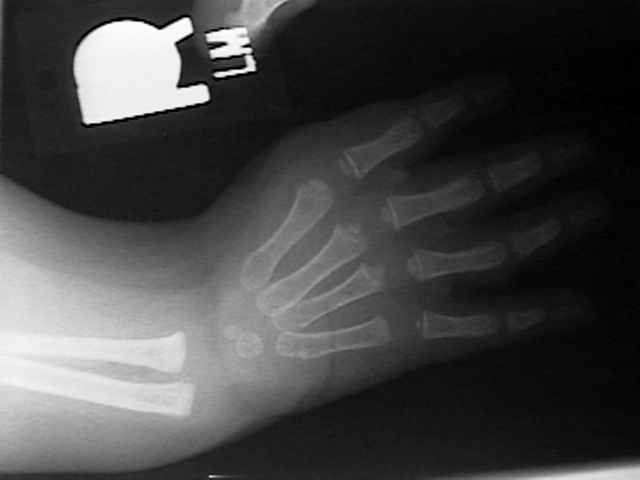

Radiographs

HL4